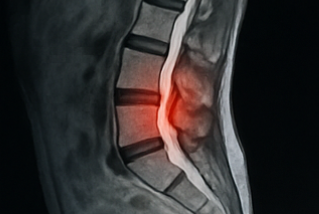

허리디스크(추간판 탈출증)

척추 뼈와 뼈 사이 있는 추간판이 돌출하거나 탈출해 신경을 압박하면 허리통증 원인으로 자주 지목됩니다. 디스크가 밀려 나가면 다리 저림, 감각 이상을 동반하기도 해요. 중년 이후에 특히 주의해야 하는 허리통증 원인이죠.

척추관 협착증

허리 속 신경이 지나는 통로가 좁아지는 상태가 척추관 협착증입니다. 허리통증 원인 중 이 질환은 특히 보행 시 통증이 심해지는 특징이 있어요. 오래 걷다 보면 다리가 무겁고 통증이 와서 멈췄다 다시 걷는 증상이 나타납니다.